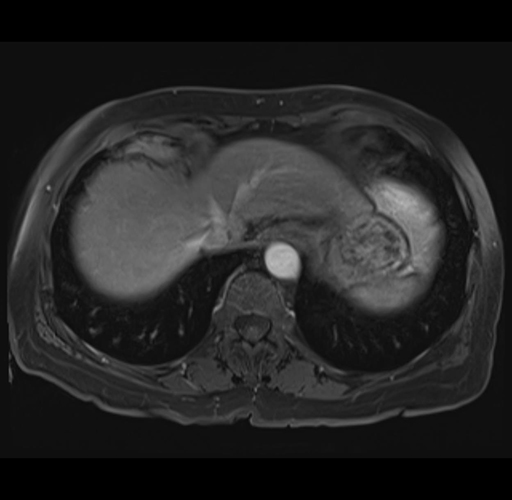

MRI T1